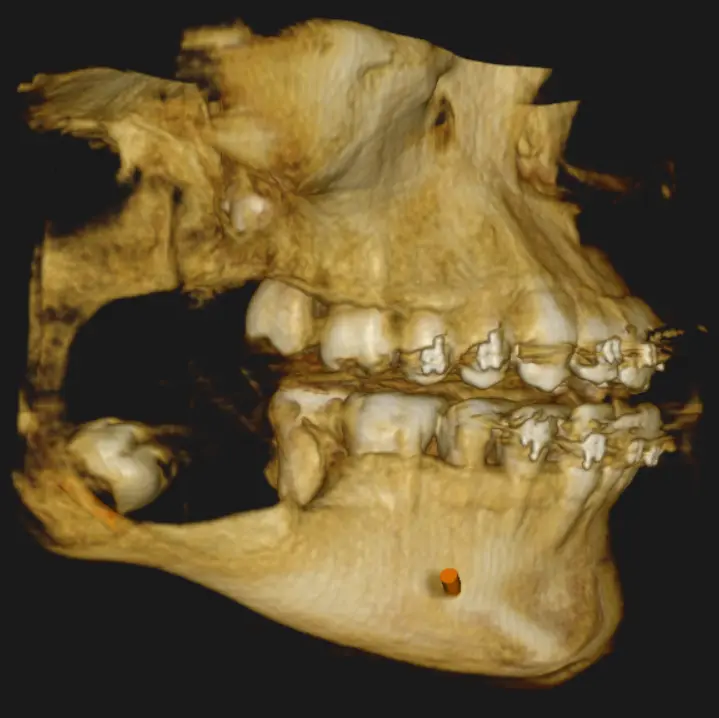

En las reconstrucciones 3D y cortes multiplanares (ver Fig 1, 2 y 3) se observa lesión hipodensa, unilocular, ubicado en rama mandibular, expandiéndose desde la rama ascendente mandibular hasta el ángulo y parte posterior del cuerpo mandibular, su contenido es homogéneo, involucra al germen de la pieza dentaria 48. Desplaza el conducto hasta la basilar, expande tabla lingual y vestibular.

En cortes coronales (Fig. 4) se aprecia los bordes definidos y parcialmente corticalizados que trata de delimitar la lesion, los cuales se encuentran sumamente adelgazados, como así también el desplazamiento de la hacia lingual pieza dentaria 47, y el desplazamiento de la pd 48 hacia la basal y hacia vestibular, los signos tomográficos nos llegavan a un diagnóstico presuntivo de Ameloblastoma Uniquístico. Se recomienda al profecional un estudio de Biopsia para tener un diagnóstico de certeza.